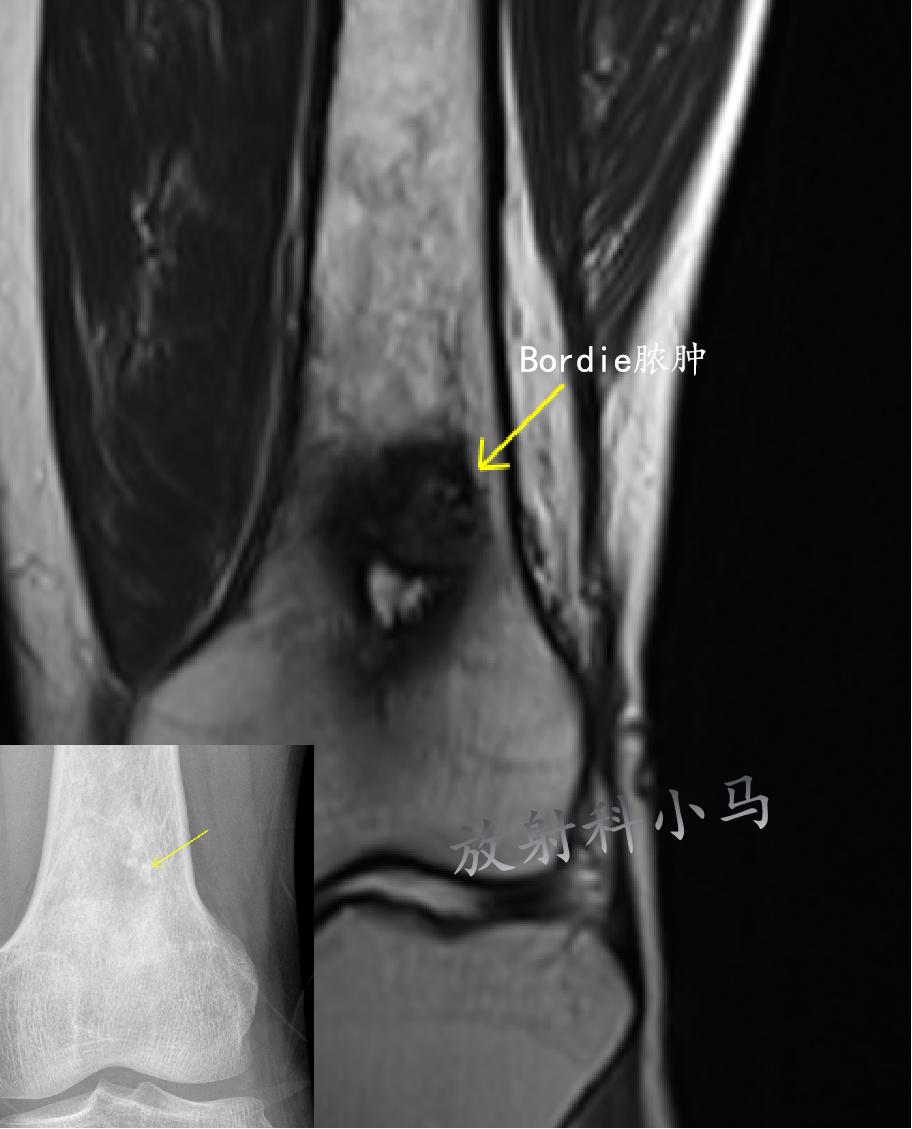

Brodie脓肿:相对静止的局限性骨内脓肿,表现为干端囊性病变,周围有硬化骨区,病灶长轴与骨干长轴相一致,早期病灶边缘模糊,逐渐边缘清晰硬化。 多见于儿童/青年,好发于长骨干端,主要表现为骨质破坏,随病变进展,周围出现反应性骨硬化,骨膜新生骨/死骨均少见。 X线及CT表现:长骨干骺端中心部位的圆形骨质破坏区,边缘较整齐,周围有一环形骨质硬化带。破坏区中偶尔可见有小死骨。 MR表现:局限性囊性病灶,边缘可见环状低信号环,病灶内脓液呈稍长T1稍长T2信号影,DWI呈高信号。